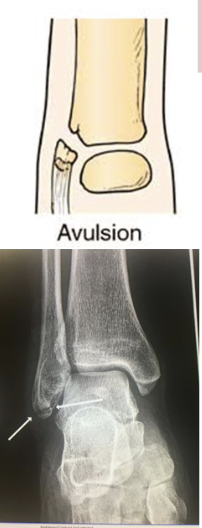

What type of fracture is this?

Avulsion

What is an avulsion fracture?

Fragment of bone is pulled away an attached tendon or ligament